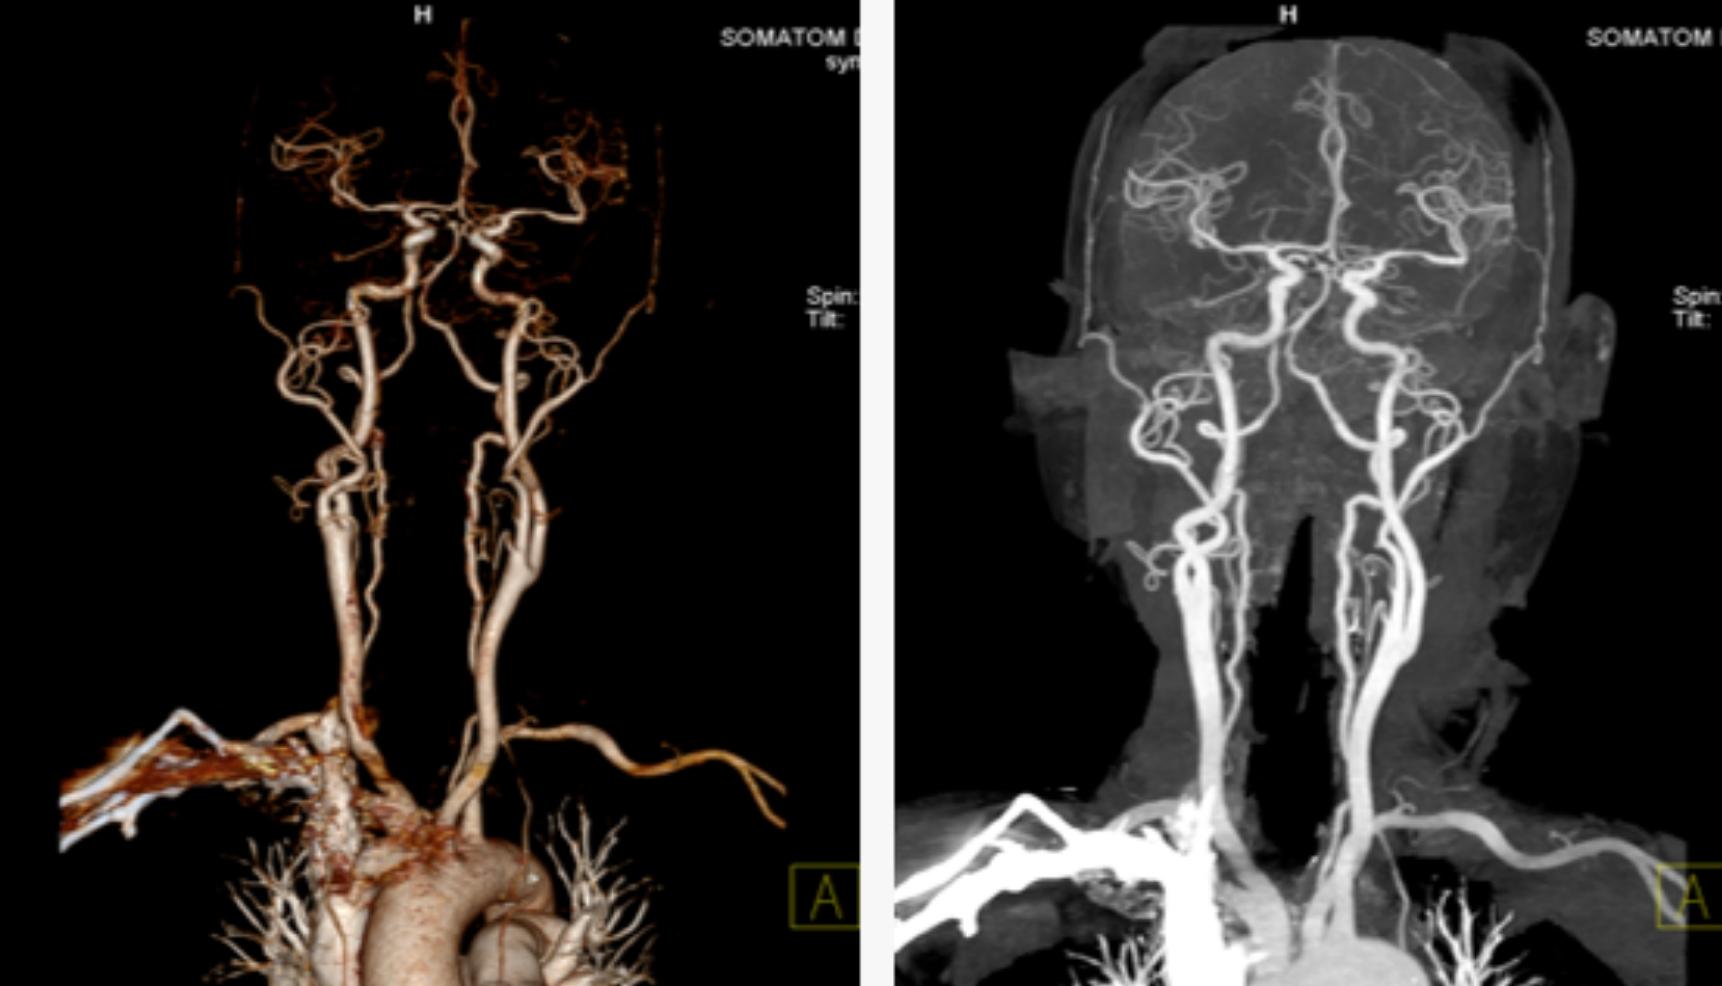

用該設(shè)備做心血管系統(tǒng)檢查,能得到對(duì)比度極佳的血管圖像。大大提高了診療的精準(zhǔn)度及工作效率,有利于醫(yī)生及早發(fā)現(xiàn)微小病灶。

通過該新型CT,不僅年老體弱的病人可以接受CT冠脈造影檢查,得到的CT圖片質(zhì)量也非常清晰,對(duì)臨床診斷的價(jià)值更大。

該設(shè)備,可以在短時(shí)間完成對(duì)冠狀動(dòng)脈缺血、肺栓塞、主動(dòng)脈瘤的一站式檢查,也可在在短時(shí)間完成對(duì)頭部血管、頸部血管、腦實(shí)質(zhì)血液灌注的一站式檢查,為腦卒中和急性胸痛患者的早期診斷和治療能力贏得黃金時(shí)間。